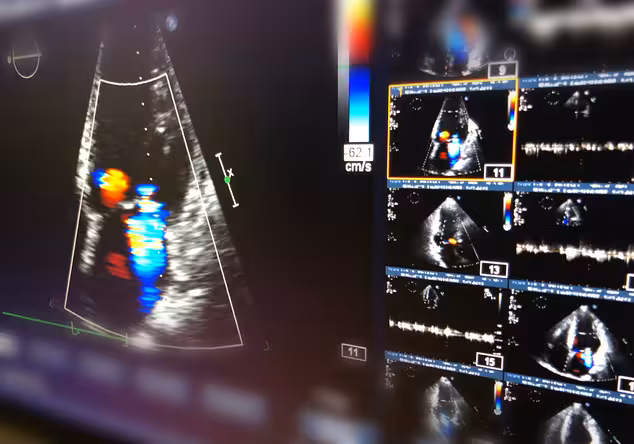

Diagnose

Zur Erkennung von Herzklappenfehlern werden alle relevanten diagnostischen Verfahren der modernen Kardiologie eingesetzt.